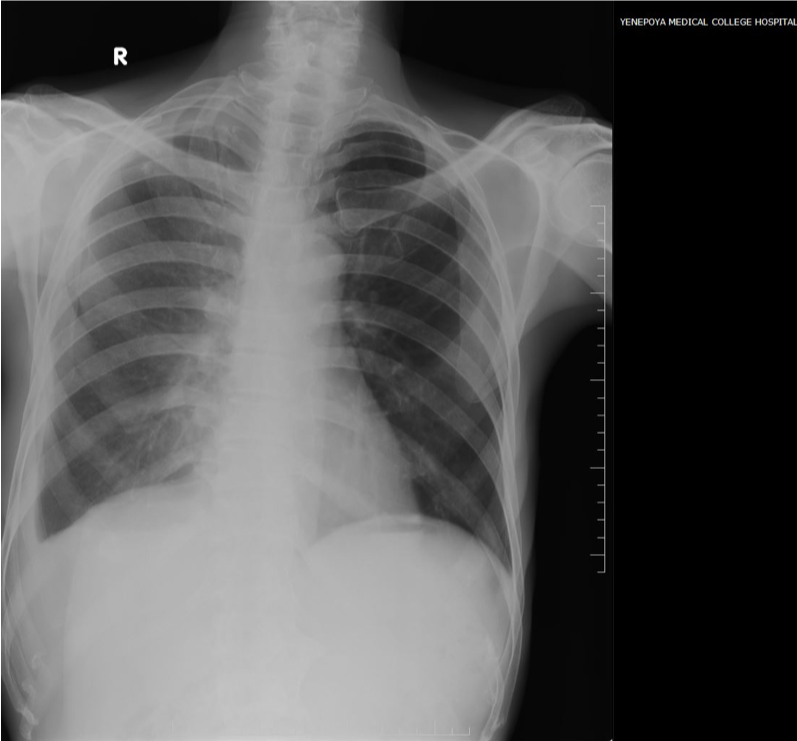

Chest X-ray shows mild blunting of costophrenic angle( )